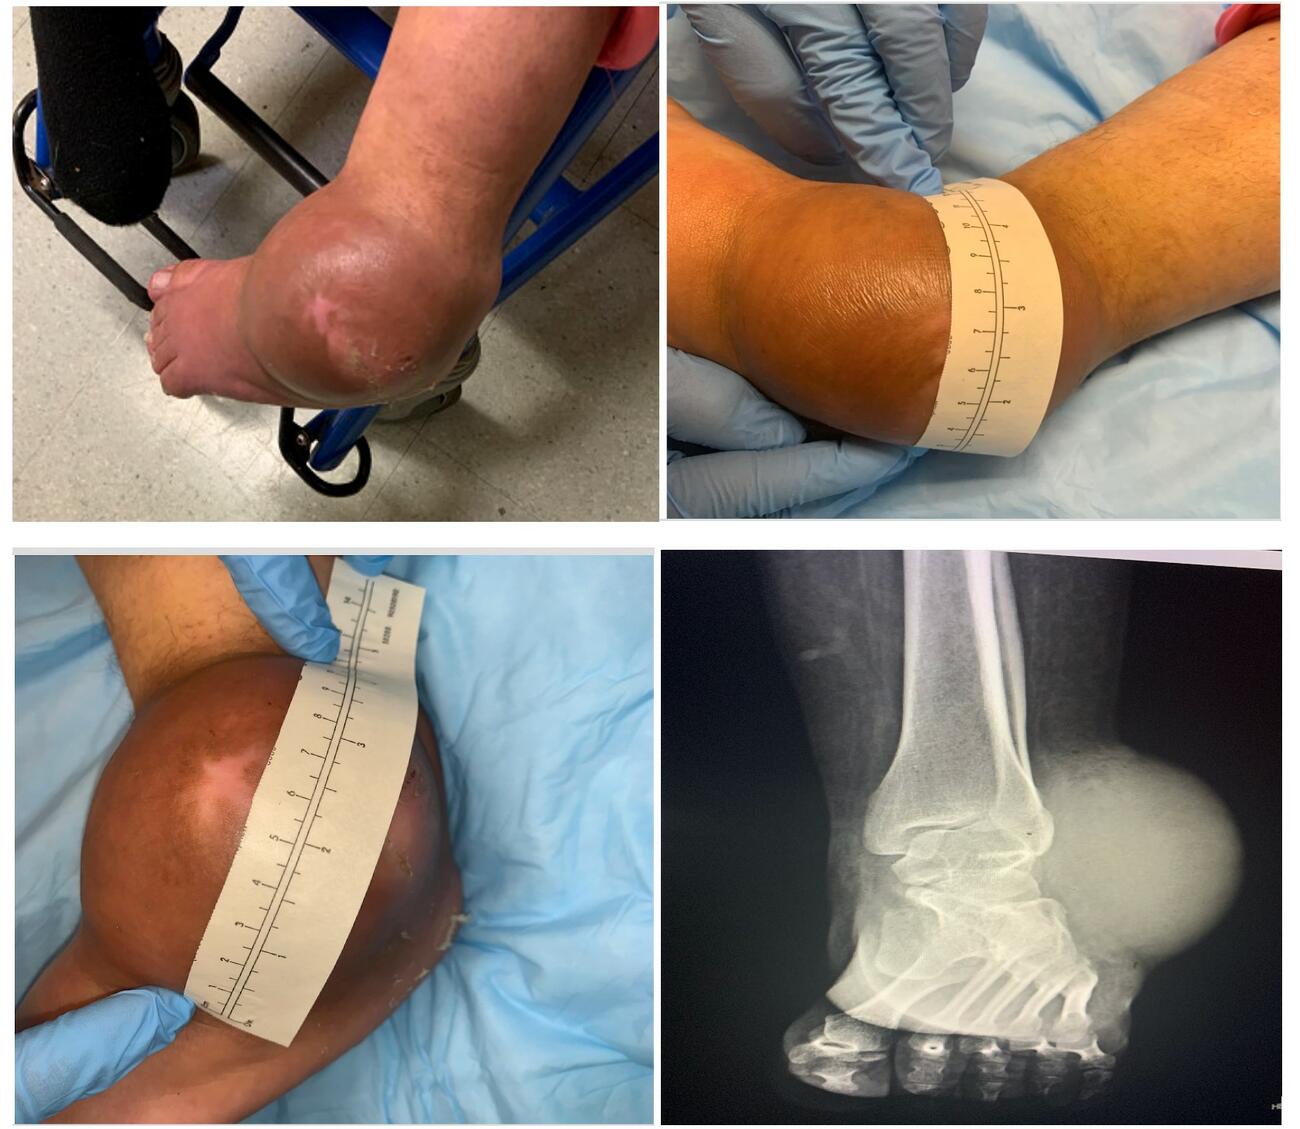

A physical exam of the left ankle demonstrated a large, fluctuant soft tissue mass adjacent to the lateral malleolus (see first photo above). The area exhibited focal edema and erythema with a notable sinus tract and purulent drainage. Initial attempts at obtaining an IV and blood work proved difficult due to the patient’s excitability and lack of cooperation. The patient quickly became agitated when staff approached with medications or to discuss the treatment plan. The staff allowed the patient time to acclimate and familiarize herself with the room before additional attempts. Once obtained, labs and vitals revealed tachycardia along with leukocytosis, lactic acidosis, and elevated erythrocyte sedimentation rate (ESR) and C-reactive protein (CRP). The team decided to take the patient to the operating room for an urgent incision and drainage with ankle wound exploration.

After achieving mild sedation, we brought the patient to the operating room for the planned procedure and administered local anesthesia. Surgery commenced, and we expressed a moderate amount of purulent fluid from the affected area. Further wound exploration revealed a firm, heavily encapsulated mass, which we excised (see second photo above).

The patient tolerated the surgery appropriately under sedation and local anesthesia. The patient began IV antibiotics, and throughout the hospital stay had local wound care daily. In order to continue to build rapport, increase familiarity, and develop a routine for the patient, the same surgeon performed the dressing changes at the same time each day. She returned to the OR days later for a successful repeat washout and closure. Postoperative films demonstrated a significant decrease in the soft tissue envelope (see third photo above). The interdisciplinary perioperative evaluation and management allowed a favorable outcome in this patient's care.